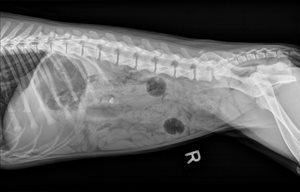

If you can see four Nerf balls in the radiograph (on top of this post), you would have agreed with our team. We suspected there was two Nerf balls in the stomach and another two in the intestines. Taking into account the frequent gagging for the past couple weeks, combined with the current acute vomiting, we determined the Nerf balls were not moving through the GI tract on their own. We suggested surgical intervention and the family agreed. Given Molly’s age and that she would already be under anesthesia, we recommended spaying her and removing the two lingering puppy teeth. This was a big day for Molly and her family.